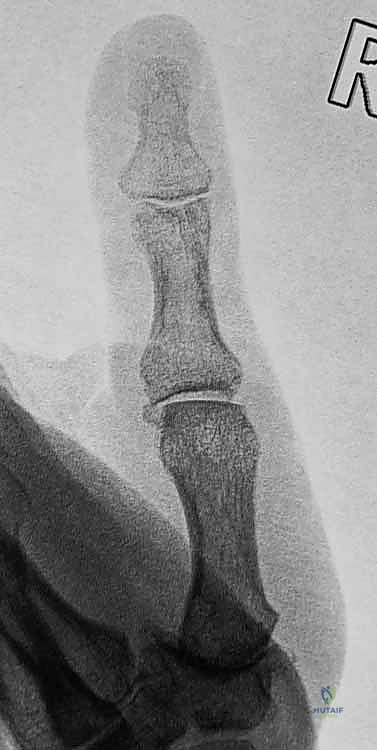

2. التصوير بالأشعة السينية (X-rays)

يُعد التصوير الشعاعي الخطوة الأولى لاستبعاد وجود كسور مصاحبة. في كثير من الأحيان، ينسلخ الرباط ويسحب معه قطعة صغيرة من العظم (Avulsion fracture). كما يتم أخذ صور أشعة تحت الإجهاد (Stress X-rays) لتوثيق عدم الاستقرار.

- الرباط الجانبي الزندي (Ulnar Collateral Ligament - UCL): يقع في الجزء الداخلي من المفصل (جهة السبابة). وهو الرباط الأكثر عرضة للإصابة والتمزق. وظيفته الأساسية هي منع الإبهام من الانحناء المفرط للخارج أثناء الإمساك بالأشياء.

- الصفيحة الراحية (Volar Plate): هيكل غضروفي ليفي قوي يقع أسفل المفصل، يمنع فرط التمدد (Hyperextension) للخلف.